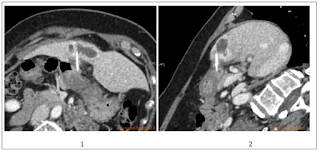

1% [1]. Hepatic #pyogenic abscess resulting from foreign body migration

is even rare [2]. Among the reported patients, most of them failed to

recall the time of ingestion and the type of foreign body. The disease

severity of hepatic abscess ranged from indolent chronic infection to #life-threatening septic shock, but the treatment was similarly composed

of adequate drainage and targeted antibiotics [3]. Regard the rare but

specific spectrum of secondary hepatic abscess induced by #foreign body ingestion, removal of the migrated foreign body is crucial in

controlling the infection [4].